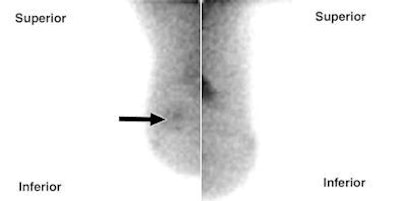

| Craniocaudal breast-specific gamma images of left (above left) and right (above right) breasts and mediolateral oblique images of left (below left) and right (below right) breasts show increased uptake at 12-o'clock position in right breast (arrows) as well as increased uptake in upper outer quadrant of left breast. |

![]() |